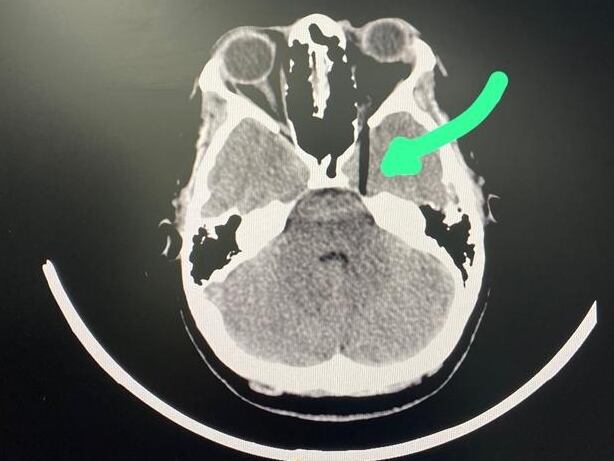

“Ese pincho de bambú estuvo a un milímetro de llegar a mi cerebro, en la radiografía se puede apreciar, ‘está muy cerquita’. La vista ya no la voy a poder recuperar según lo que me dicen los doctores, porque el pincho dañó al nervio óptico, pero yo buscaré otras opiniones de otros expertos en la salud”, explicó